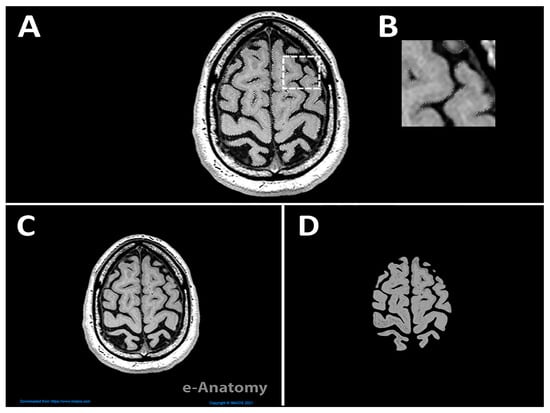

- Step 2: Edit the raw images in Photoshop to isolate the brain from remaining structures of the head.

2.1. Data Collection

2.2. Computer-Aided Modeling